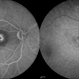

- Atypical central serous chorioretinopathy

- chronic central serous chorioretinopathy (CSCR), retinal pigment epithelium atrophy

- Left eye extensive RPE atrophy at macula from chronic central serous chrioretinopathy in a 62-year-old gentleman. The right eye had a similar picture.